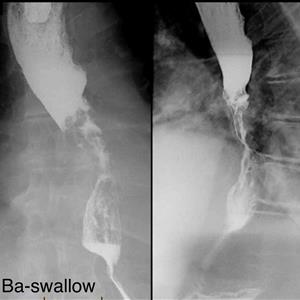

BARIUM SWALLOW

IS IS A SERIAL LIVE X.RAYS TO BE TAKEN ON IITV ( X.RAY MACHINE) WHILE PATIENT IS SWALLOWING

SEMI-SOLID OR LIQUID BARIUM ( A CONTRAST MEDIUM)

4 TO 8 X RAYS IN SUCCESSION TO BE TAKEN IN FEW MINUTES